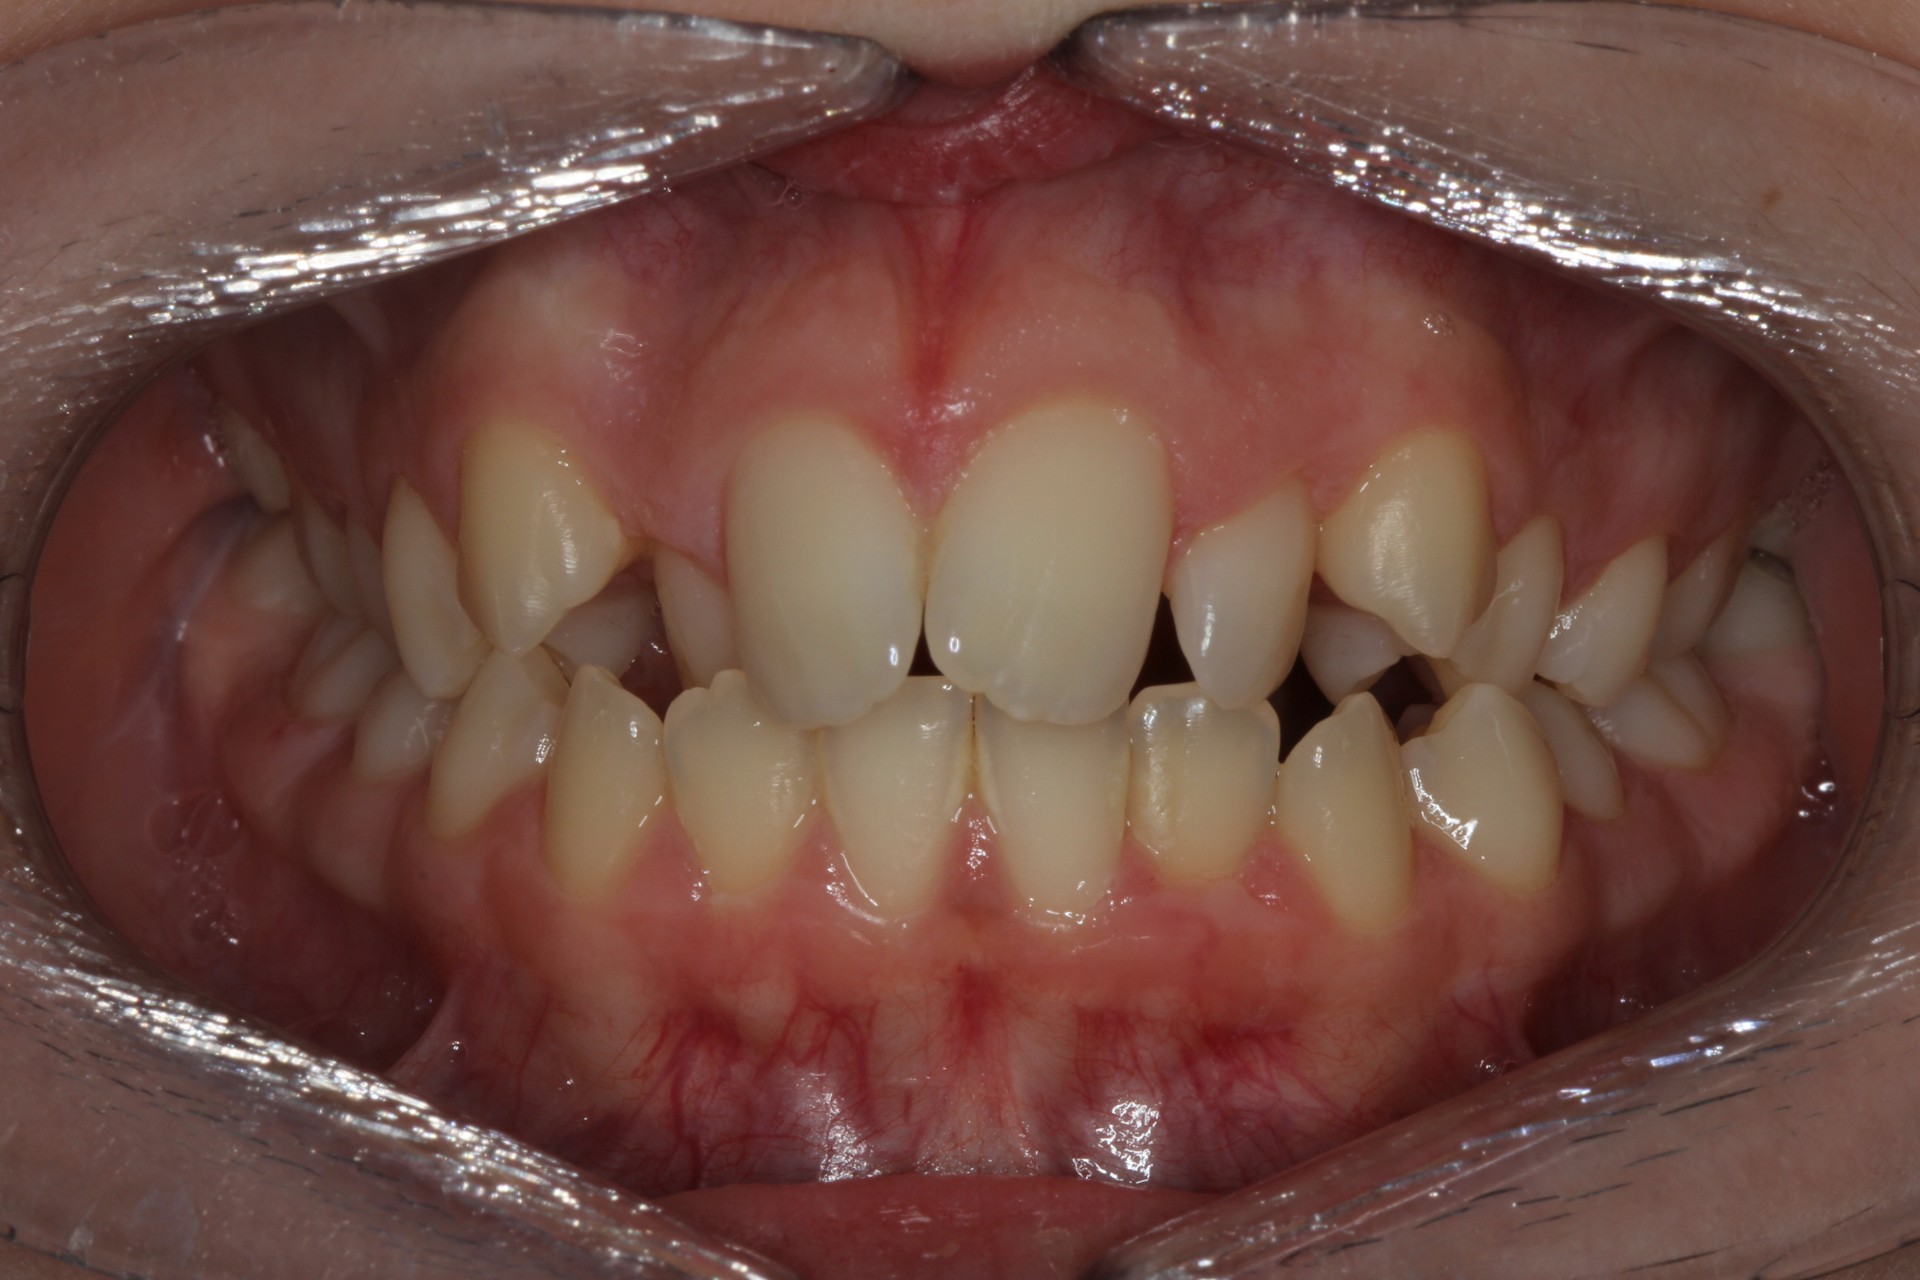

Crowding – Child case